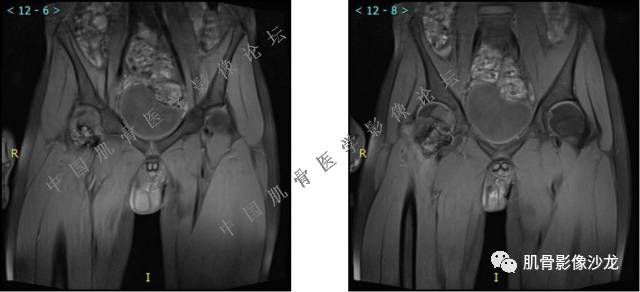

主诉:左髋疼痛1月余

现病史:患者1月余前无明显诱因出现左髋部疼痛,无明显活动受限,当地医院行X线检查,提示左股骨颈异常密度。遂来我院就诊。

既往史:曾患乙型肝炎,未正规治疗,目前无症状。

葛英霖 20:5 4 常规纤维类的多一些,冠状位没有看到明显脂肪。纤维结构不良、纤维组织细胞瘤、软粘纤之类。

夏威夷的风 20:55 大方向纤维类病变

夏威夷的风 20:58 强化渐进性强化吧 边界清晰 里面也见线状低信号

飞鹰行动 21:01 良性纤维组织细胞瘤内部可以有少量脂肪

X(CT、MR)战警 21:01 泡沫细胞被吞噬后形成脂肪信号, bfh可以有脂肪条带样改变

Echo 21:04 总之这例就是各位老师说的硬化边明显,没有软组织肿块,没有侵犯,考虑良性病变,增强渐进性强化,所以考虑BFH